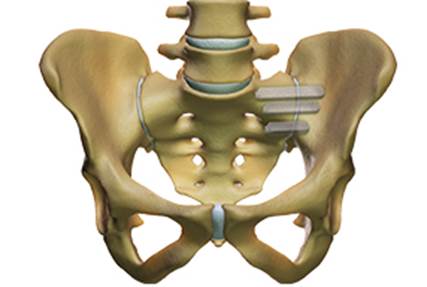

El tractament quirúrgic de l’articulació sacroilíaca dolorosa està indicat únicament en casos d’en què la teràpia conservadora ha fracassat durant un mínim de 6 mesos. Davant d’un dolor persistent i crònic es pot realitzar una cirurgia mínimament invasiva que consisteix en la introducció percutània de tres implantes de titani de perfil triangular mitjançant l’ili i del sacre. D’aquesta manera queda bloquejada l’articulació sacre-ilíaca en tots els seus graus de llibertat.

Caracterització de fusió quirúrgica percutània de l’articulació

sacre-ilíaca esquerra mitjançant 3 implants de titani de perfil triangular..